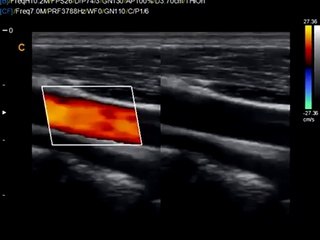

Chison Sontotouch 30 Touch screen color doppler Ultrasound